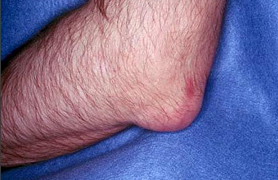

【易发部位】脚拇指关节、拇趾跖关节、跗跖关节、踝关节、手指关节,掌指关节、腕关节、肘关节、膝关节、耳廓。

【典型症状】膝肿痛、关节痛、关节肿胀、尿酸高、发热、厌食、鹤膝风。